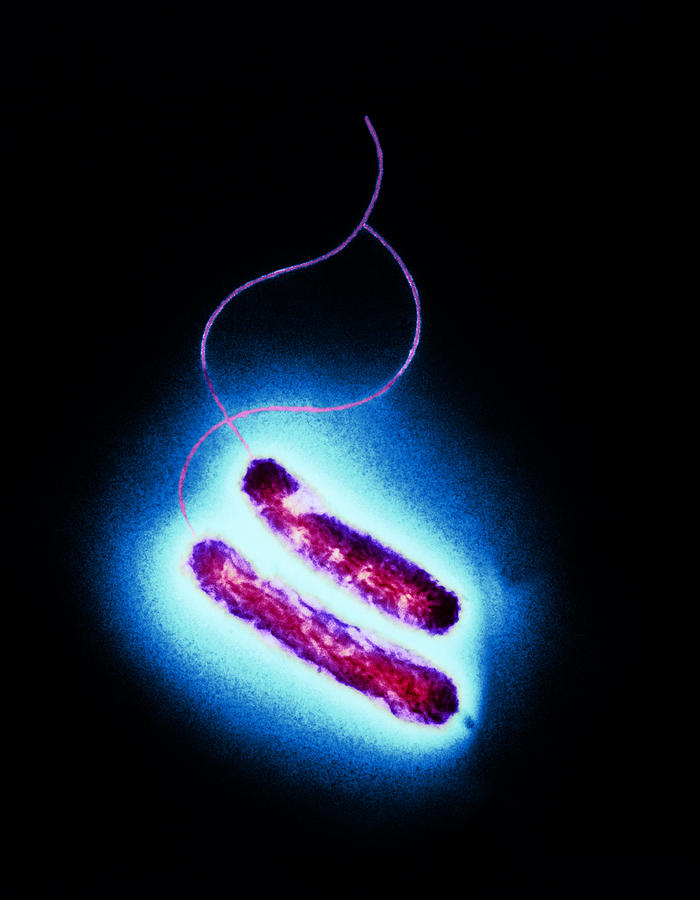

Кампилобактер фетус: патогенез и инфекции